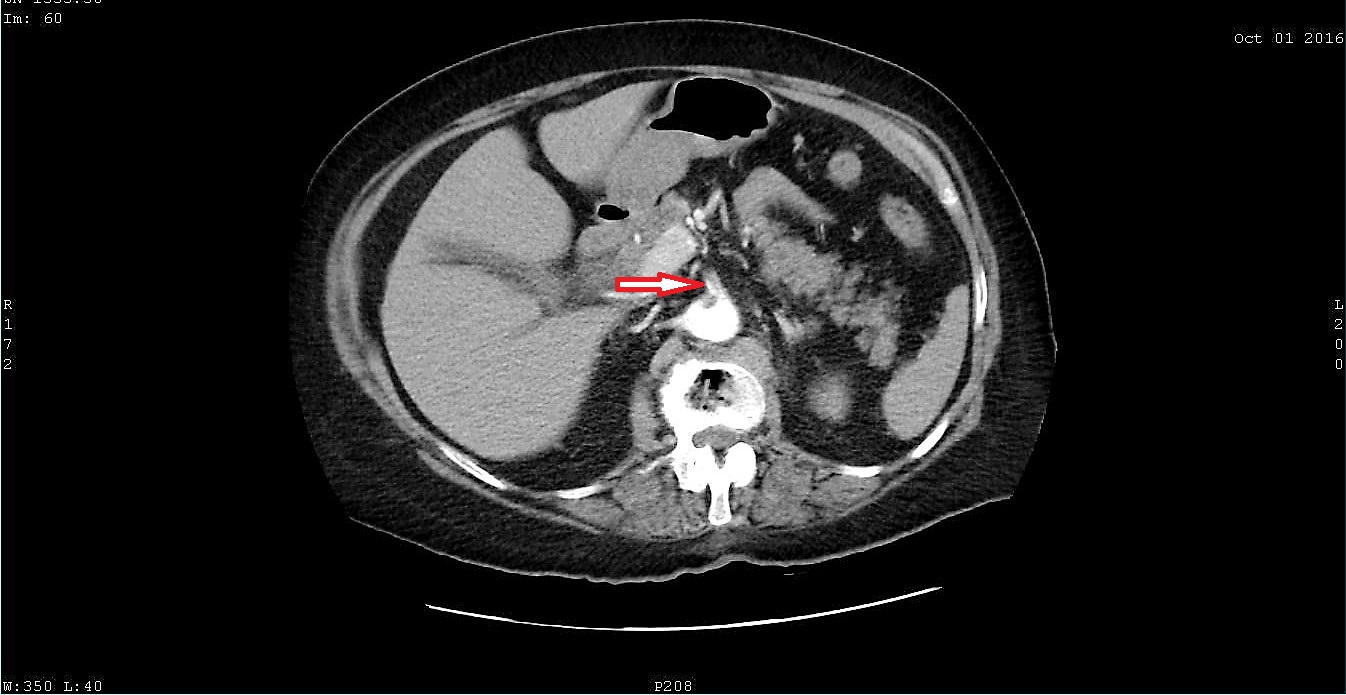

Paradoxical embolism is an uncommon cause of arterial occlusion with a high mortality burden. Current evidence suggests that patent foramen ovale is the most important etiological factor of paradoxical embolism, by acting as a pathway for a thromboembolic material originating from the peripheral veins, passing through the lungs and entering the systemic circulation. Here we present a case of paradoxical embolism in the mesenteric and renal arteries associated with pulmonary embolism and deep vein thrombosis in an elderly woman with no predisposing risk factor. A diagnosis of paradoxical embolism was considered and the presence of a patent foramen ovale was consequently confirmed with a transesophageal echocardiography. Urgent thrombolysis saved the life of the patient. Paradoxical embolism represents an emergency and therefore prompt diagnosis and initiation of therapy may prevent adverse outcomes.